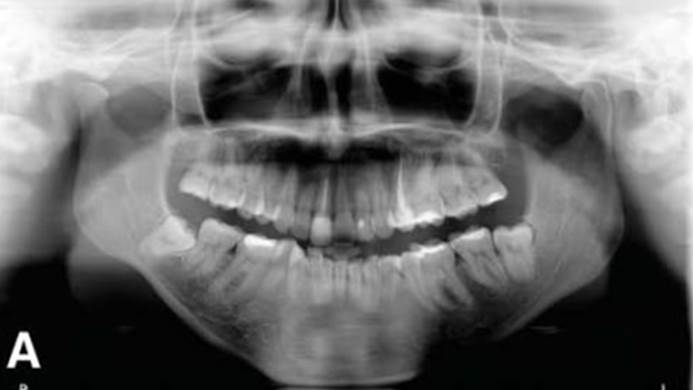

Clinical case: Immediate post-extraction insertion of implant & immediate loading

- Courtesy of Prof. Giuseppe Luongo, Italy -

Keywords

AnyRidge, immediate loading, single implant, multicenter study, maxillary anterior, Prof. Giuseppe Luongo, single replacement

Products:

AnyRidge implant system

Reference

Immediate functional loading of single implants: a multicenter study with 4 years of follow-up

/J Dent Res Dent Clin Dent Prospect 2018; 12(1):26-37 | doi: 10.15171/joddd.2018.005

https://www.ncbi.nlm.nih.gov/pubmed/29732018